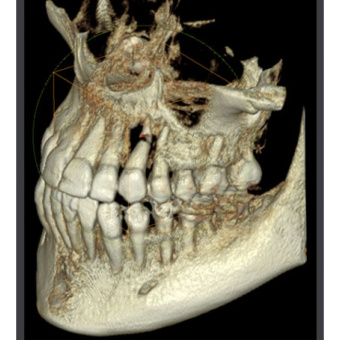

Ортопантомограф RAYSCAN является передовым диагностическим оборудованием, в котором применяются 2 сенсора: высококачественный плоский сенсор HAMAMATSU (Япония) для панорамной съёмки и отдельный сканирующий сенсор, которые обеспечивают чёткое изображение с первого раза (даже волос и мягких тканей), последний имеет различные режимы сканирования.

- тип излучения: конусный луч

- бит данных: 14 бит

- размер изображения: 150 мм макс для панорамы, 260х225 мм для цефалометрии